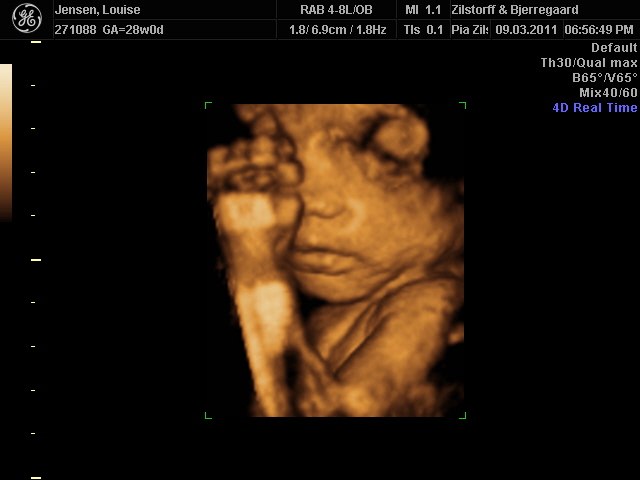

Jeg og kæresten var til 3D-scanning igår - sikke da en oplevelse  - det er da helt klart alle pengene værd ..

Hold da op en smækker lækker baby'boy der gemmer sig derinde i hulen, fy føj mor her fik tårere i øjne .. sikke da alt den kærliighed der væltede over mig .. suk suk

han ligner han far meget  - det er så vidunderligt hvad man dog kan se..

perfekt hjertelyd og vægten siger 1166 og er i uge 29 nu